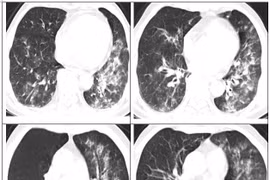

Sau hơn 1 tháng hút thuốc điện tử nam thanh niên đã phải nhập viện vì viêm màng ngoài tim và viêm phổi. Có ít nhất 215 trường hợp gặp các vấn đề nghiêm trọng về phổi liên quan đến hút thuốc lá điện tử nên cần chú ý.